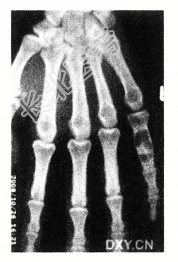

- [材料题] 男性,28岁。偶尔发现右手第5近节指骨肿胀。查体:右手掌肿块,质硬,无明显压痛,无发热。进行了右手X线平片CT检查(下图)。

- 单项选择题1.病变发生部位在

A、近节指骨骨端

B、近节指骨骨干

C、近节指骨骨骺

D、近节指骨干骺端

E、指骨周围软组织

- 单项选择题2.对于此病变影像学征象的描述,不正确的是

A、右手小指骨干囊性膨胀性溶骨破坏

B、边缘清楚可见硬化缘

C、病灶内可见不规则钙化

D、可见骨膜反应

E、病变为偏心性生长

- 单项选择题3.此病变最可能的诊断是

A、骨囊肿

B、内生软骨瘤

C、骨结核

D、成软骨细胞瘤

E、骨巨细胞瘤